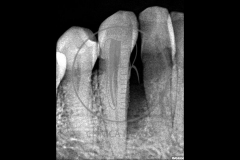

Tratamiento de defectos periodontales infraóseos en sector antero-inferior empleando gel de amelogeninas (Emdogain®) en combinación con un aloinjerto óseo (Biobank®). Paciente de 64 años, sin problemas médicos de relevancia, que presenta una periodontitis leve generalizada, pero asociada a presencia de defectos óseos verticales profundos a nivel de los espacios interdentales entre los caninos y los incisivos laterales inferiores. Tras la pertinente fase higiénica, se llevó a cabo una cirugía periodontal regenerativa, en la que, tras eliminar el cálculo subgingival (factor causal), se empleó una combinación de amelogeninas con un aloinjerto, para promover la regeneración tisular del periodonto perdido. Las imágenes clínicas y radiológicas, al año de seguimiento, reflejan un resultado terapéutico óptimo, con regeneración completa del tejido periodontal y mejora del pronóstico de los dientes involucrados.